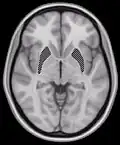

![]() Coronal section of brain through intermediate mass of third ventricle. (Putamen labeled at top.) | |